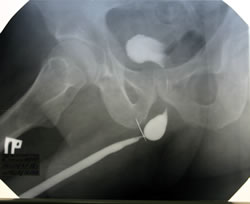

Методика и показания к восходящей ретроградной уретрографии